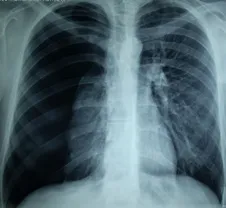

d.Röntgen filmi çektirilip, ciğerin söndüğü sonucuna vararak.